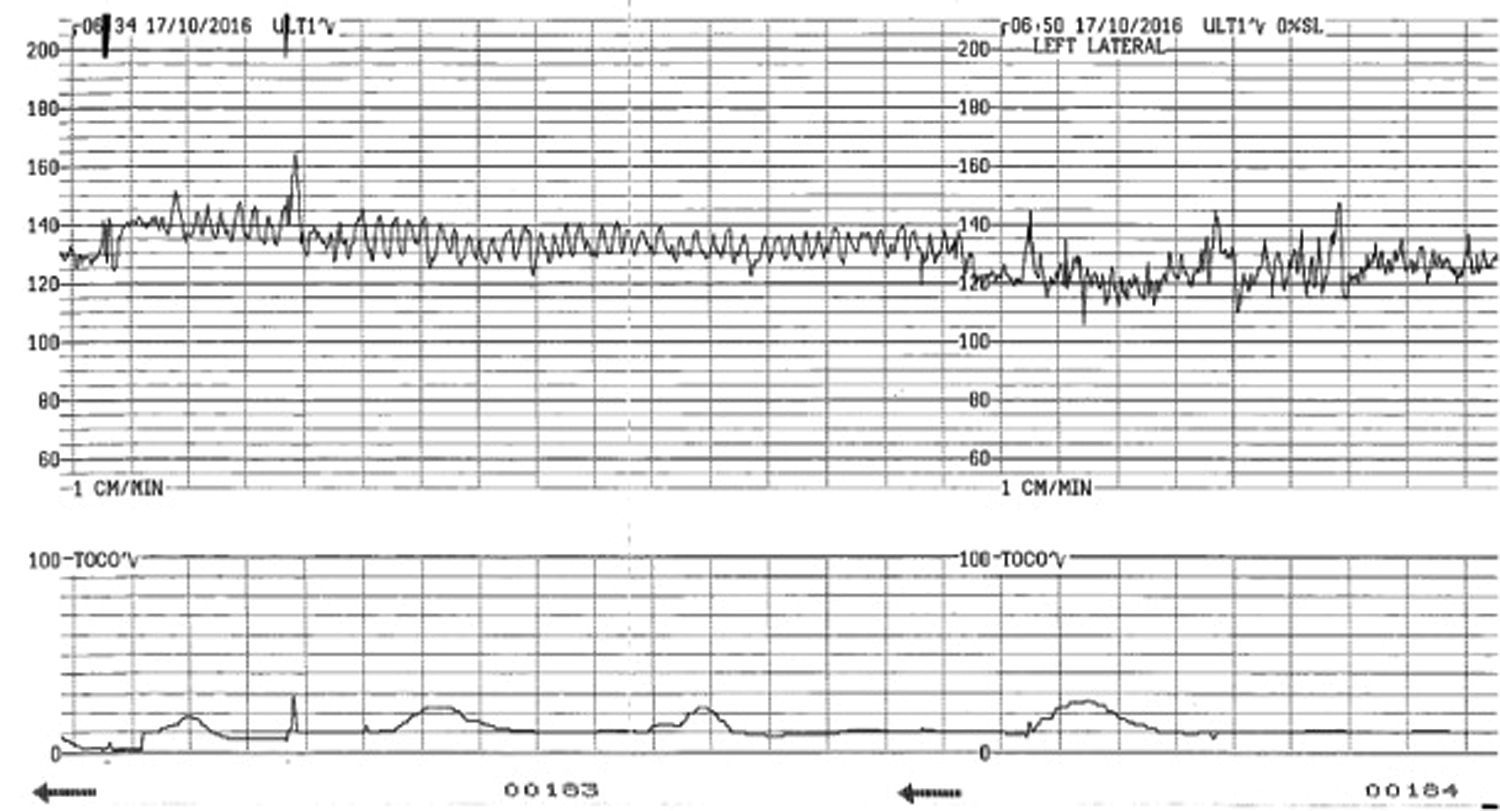

Are you curious about sinusoidal fetal heart rate patterns? You’re in the right place! Sinusoidal fetal heart rate patterns are a unique type of heart rate pattern that can be observed during labor and delivery.

These patterns are characterized by a smooth, regular, and symmetrical waveform on the fetal heart rate monitor. They are different from the typical heart rate patterns seen during labor and delivery and may indicate certain underlying conditions.

sinusoidal fetal heart rate pattern

Understanding Sinusoidal Fetal Heart Rate Patterns

Sinusoidal fetal heart rate patterns can be a cause for concern as they may be associated with fetal distress. It is important for healthcare providers to monitor these patterns closely and take appropriate action to ensure the well-being of both the mother and the baby.

There are various factors that can contribute to the development of sinusoidal fetal heart rate patterns, including fetal anemia, maternal bleeding, and certain medications. It is essential for healthcare providers to identify the underlying cause of these patterns and address it promptly.

If sinusoidal fetal heart rate patterns are detected during labor and delivery, healthcare providers may recommend additional tests and interventions to assess the baby’s well-being and ensure a safe delivery. Close monitoring and timely intervention can help prevent complications and improve outcomes for both the mother and the baby.

In conclusion, sinusoidal fetal heart rate patterns are a unique type of heart rate pattern that can be observed during labor and delivery. It is important for healthcare providers to monitor these patterns closely and take appropriate action to ensure the well-being of both the mother and the baby.